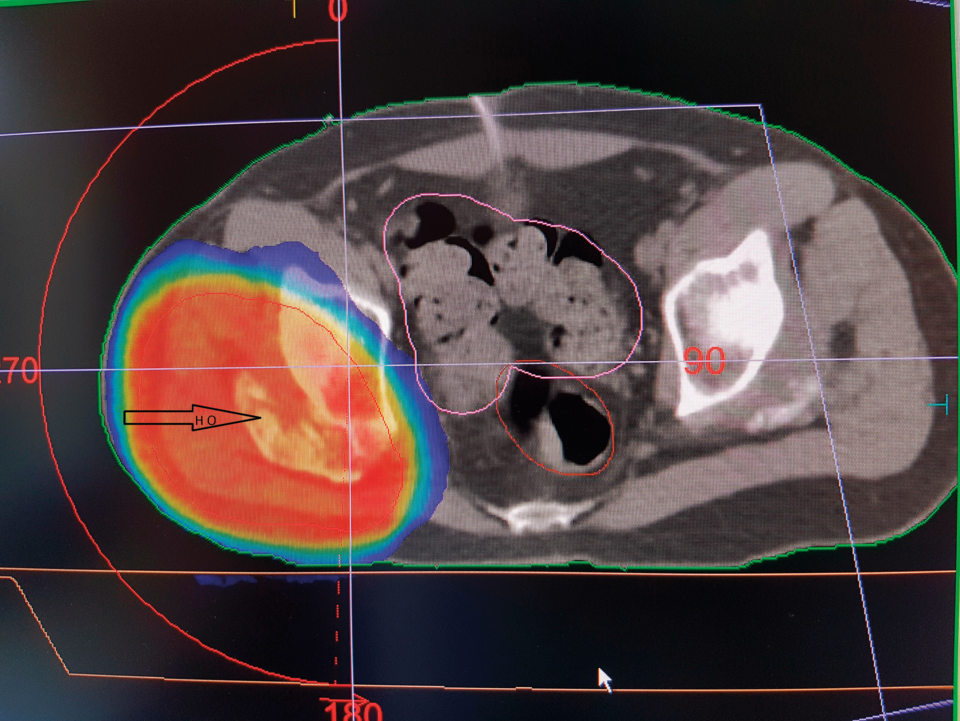

Die volumenmodulierte Strahlentherapie einer heterotropen Ossifikation am rechten Hüftgelenk stellt keine größere Belastung für die Beckenorgane dar. Die volumenmodulierte Strahlentherapie einer heterotropen Ossifikation am rechten Hüftgelenk stellt keine größere Belastung für die Beckenorgane dar. © Schneider T, Schneider­ K. internistische praxis 2019; 61: 284-300 © Medien­gruppe Oberfranken - Fachverlage GmbH & Co. KG, Kulmbach